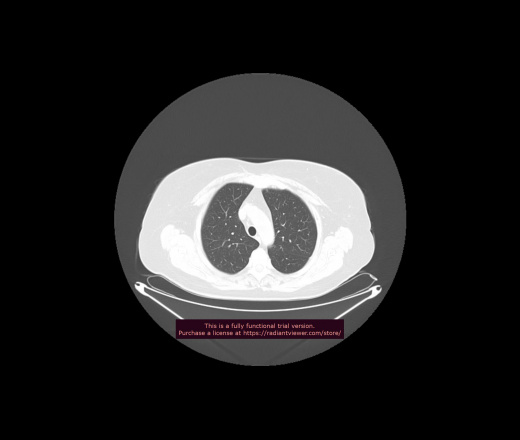

Уважаемые коллеги, если имеется интерес, сможете ли Вы спрогнозировать дальнейшее +-одинаковое течение процесса у 4 данных разных пациентов? Зацепиться где-то можно очень просто, где-то нельзя.